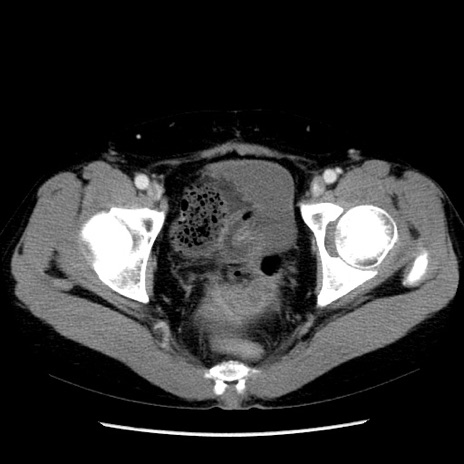

症例6(横断像)

【症例】50歳代女性

【主訴】下腹部痛

【既往歴】卵巣癌術後(8年前に当院で卵巣摘出)

【身体所見】 意識清明、腹部:平坦、腸蠕動音→、やや硬、下腹部自発痛・圧痛あり、反跳痛あり、筋性防御なし。

【データ】WBC 16000、CRP 0.01